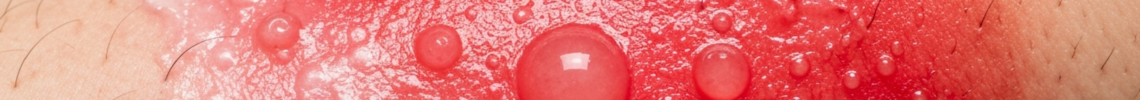

The hallmark of a second-degree burn is the presence of blisters. These fluid-filled sacs typically form within hours of the injury, though sometimes they may not appear for a day or more. In second-degree burn symptoms pictures, these blisters can range in size from small, pin-prick vesicles to large, tense bullae covering significant areas. The fluid within the blisters is usually clear or slightly yellowish, consisting of plasma that has leaked from damaged capillaries. The integrity of these blisters is a key indicator; intact blisters suggest a sterile environment, while ruptured blisters indicate a breach in the skin barrier, increasing the risk of infection.

Beyond blisters, the skin affected by a second-degree burn exhibits a characteristic color and texture. It is typically bright red or mottled, appearing moist or glistening. This moist appearance is due to the exposure of the underlying dermis and the leakage of fluid. Unlike the dry, leathery appearance of a full-thickness burn, the moistness in a partial-thickness burn is a critical visual cue. The redness indicates increased blood flow to the damaged area as the body initiates the inflammatory response and healing process. Pressure on the affected skin often causes blanching (turning white), and upon release, the color quickly returns, indicating that capillary perfusion is still intact within the viable dermal layers. This quick capillary refill is a vital sign when assessing second-degree burn pictures.

• Blister Formation: Presence of clear or yellowish fluid-filled blisters (vesicles or bullae). Blisters may be intact or ruptured.

• Skin Color: Bright red, pink, or mottled (patchy red and white) appearance. The redness is often vivid and uniform across the affected area.

• Skin Texture: Moist, glistening, or weeping surface, indicating exposure of the underlying dermis. The texture is usually soft and pliable.

• Capillary Refill: When gently pressed, the red skin blanches (turns pale) and quickly refills with color, indicating preserved blood flow.